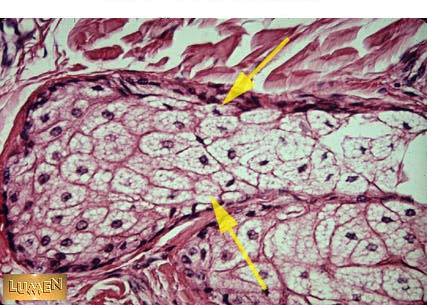

What does this gland produce?

Sebum -Oil